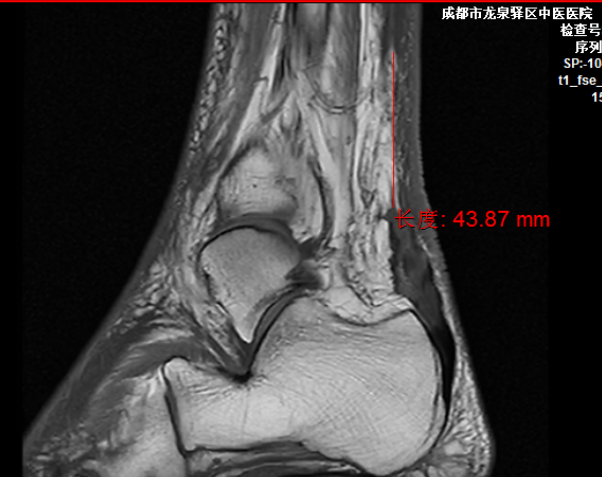

术前MRI示跟腱断裂、缺损